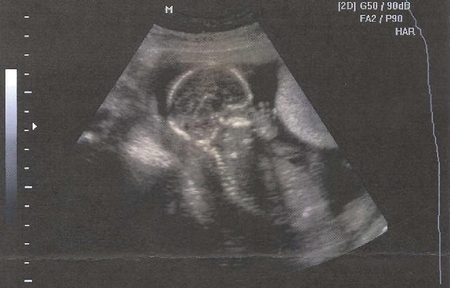

Узи № 3 (он же 2-й скрининг)

Делала в ЦИРе, с фотками и видео. Врач попалась молодая, но приятная и, по-моему, опытная девушка. Очень долго и тщательно все проверяла, измеряла, показала все в деталях :) И, наконец, мы узнали пол! Ждем мы девушку-красавицу!

Самое главное, что дочурка развивается по всем нормам, никаких отклонений не обнаружено! Чему я особенно рада!

По результатам узи мы всего на 2 дня опережаем акушерский срок.

А вот, кстати, и виновница поста:

Девочка-принцессочка это так здорово!!! Такая лапочка на второй фотке, где профиль так отлично получился!